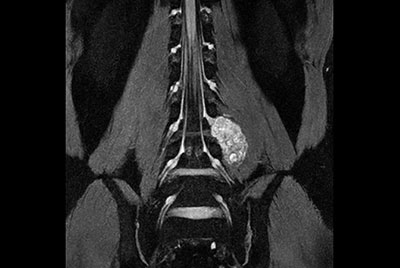

Pediatric pelvis with fistula